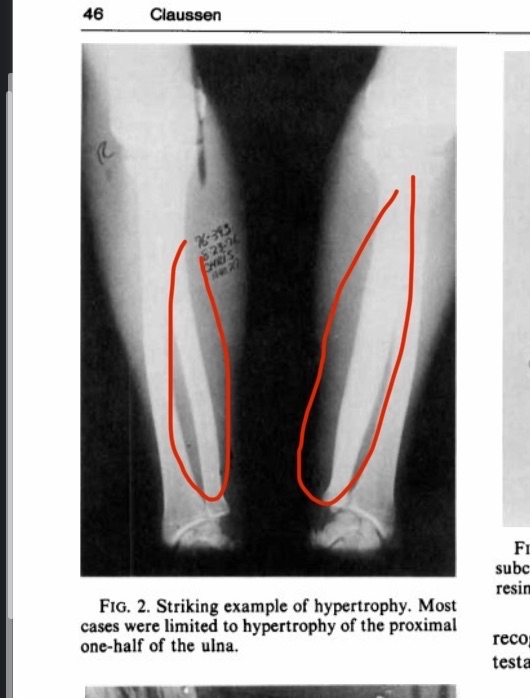

(Figure 2, an image showing bone hypertrophy, please note that the increase in diameter here was approximately 62%, but the largest increase reached 92%)

Many of you may already know about bareback rodeo, a sport that requires the rider to have their forearm directly strike the hip bone. Here is a literal excerpt from the study describing what happens: “On observing a contestant who is riding, the riding arm is noted to contact the anterior iliac crest and the heavily resined chaps (Fig. 3). The event requires strength, timing, balance, and courage. Ideally, the forearm should be tucked against the pelvis and chaps. Failure to maintain this position results in a hammering action of the forearm against the pelvis and chaps.“You don’t have to be particularly smart to understand this literally; the scientists stated that the hypertrophy that occurs is the result of direct impact or a “hammering action.”If you’re wondering about the extent of the bone growth, to be frank there was massive hypertrophy, although it varied among participants (I will explain the reasons for this variation).In one sample, the diameter of the ulna increased by 92% and the bone’s cross-sectional area by 262%, which are extremely large biological increases, especially considering participation in this sport is prohibited before age 18.Some might argue that this hypertrophy is due to muscle tension rather than direct impact on the bone, but this is incorrect for several reasons.First, many sports apply intense torsion forces to bones but do not cause even a 10% increase as observed in rodeo riders.Second, the hypertrophy occurs exclusively at the area where the ulna contacts the hip.Third, the hypertrophy was observed only in riders who did not use a saddle; the saddle acts as a barrier preventing friction and impact with the hip bone, and its absence allows direct friction and impact.Fourth, the variation in hypertrophy among participants is likely because some wore protective gear to prevent friction while others did not (see figure 2 to view the bone hypertrophy) [25].

In another study with the same objective as the first but older, we can say that they found exactly the same results massive bone hypertrophy occurred in bareback rodeo riders. Fortunately, this time the supervising researcher fully agrees with my scientific explanation for this hypertrophy. I will quote directly from him: “The hypertrophy is considered by the author to be a chronic circumferential periostitis secondary to trauma.“It seems the author completely agrees with me, explaining the hypertrophy as resulting from direct trauma to the bone (the trauma from the ulna hitting the pelvis), which leads to chronic peripheral periostitis and subsequently bone hypertrophy.This study strongly supports my theory, because how else would you explain massive bone growth resulting from periosteal inflammation (as we mentioned earlier, through hematoma formation, red blood cell coagulation, and release of inflammatory factors)? Continuing in this state eventually leads to enormous bone hypertrophy.An important point is that a rodeo round actually lasts only 8 seconds, which debunks the argument that you need to spend hours daily to do bone smashing. If that were true, how do you explain the bone hypertrophy in rodeo riders who only do very limited rounds per day?Not to mention that the bone isn’t in constant impact throughout the round, probably only 2–3 seconds in total (see figure 3 to view the hypertrophy) [26]